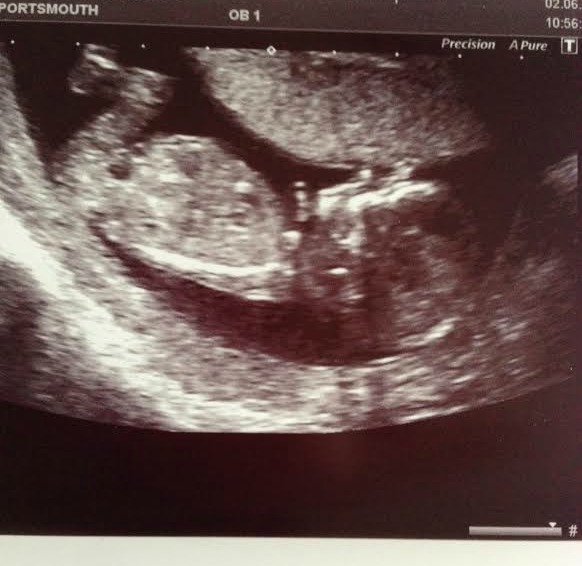

A pic (if this works) this is the clearest one we got. Baby wouldn't keep arms or legs still

I think in this one he's got his arms in front of his face (this leads me to ask - how are you referring to baby if you don't know/until you know the gender?)

I looked on facebook at friends past scan pics and they're all lovely and clear with a nice view of the head - you can see the nose and everything. Nope - not here

My little munchkin is obviously camera shy!